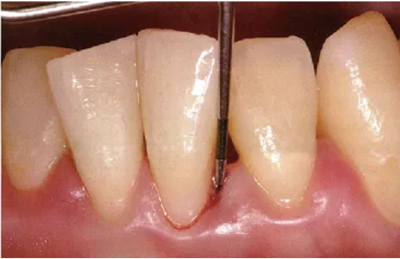

探針要與牙軸平行插入。注意不要探針的尖端離開牙面。

● 頰側(cè)、舌側(cè)探針的插入

通常與牙軸平行插入

注意盡量讓探針貼著牙面。